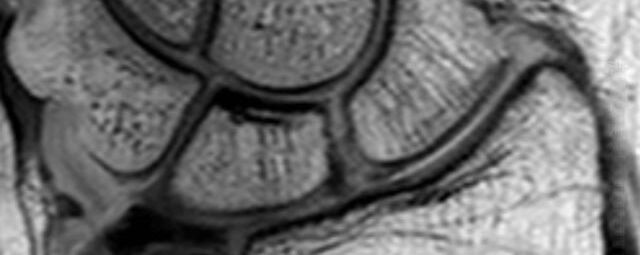

- Beurteilung von Knochen, Bändern und anderen Weichteilstrukturen der Gelenke nach Unfall.

- Arthrosediagnostik (Knorpelschaden)

- Impingement-Symptomatik

- Ursachenklärung bei wiederholter spontaner Gelenkluxation

- Ausbreitungsdiagnostik bei Gelenkentzündung, z.B. im Rahmen von rheumatischen Grunderkrankungen

- MR-Arthrographie – nach örtlicher Betäubung und gründlicher Desinfektion der Haut wird unter Lagekontrolle mit Röntgen-Durchleuchtung eine kleine Nadel in den Gelenkraum positoniert und darüber ein MR-taugliches Kontrastmittel in den Gelenkraum gespritzt. Danach wird die Nadel entfernt. Anschließend erfolgt die MRT des Gelenkes. Diese Methode stellt kleine anatomische Strukturen des Gelenkraumes verbessert dar, z.B. zur Therapieplanung vor Arthroskopie bei Sportverletzungen der Schulter oder Gelenkinstabilität.